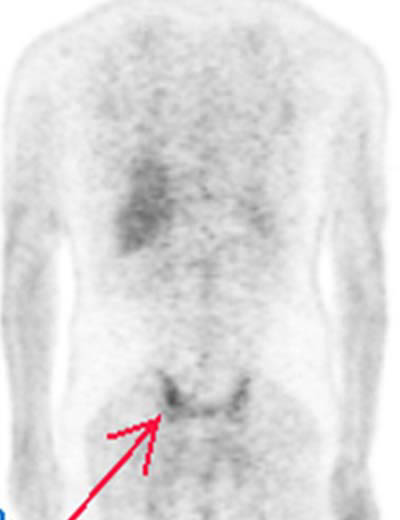

Fig. 22. - Corte coronal posterior de tomografía por emisión de positrones de cuerpo completo a nivel de articulación sacroiliaca. Varón de 40 años sin antecedentes personales. Se aprecia aumento focal del metabolismo de la [18]FDG en región sacroiliaca derecha (flecha). Posteriormente se confirmó como una sacroileitis. |